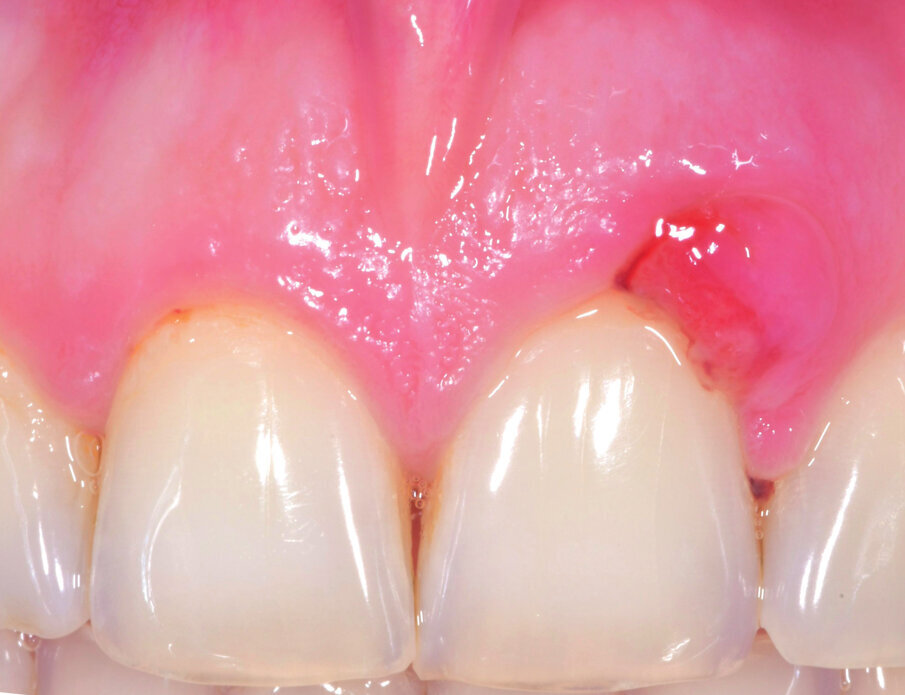

Il paziente di anni 33 viene inviato per trattamento di un gonfiore gengivale apparso circa 1 mese prima. È stato trattato con scaling e root planing senza ottenere il risultato voluto. All’esame obiettivo presenta una lieve gengivite interprossimale con infiammazione e gonfiore limitato alla parte vestibolare di 2.1 con sondaggio di 5 mm vestibolare e 7 mm disto-vestibolare (Fig. 1). La superficie della radice era stata strumentata una settimana prima e si presenta senza residui di tartaro e senza riassorbimenti esterni. Viene scelta l’applicazione di Ozosan Gel per ridurre subito i sintomi che limitavano la capacità del paziente di applicare una corretta igiene orale e per la sua azione antibatterica ma anche stimolante la guarigione. Ozosan Gel viene applicato per 8 minuti - azione anti batterica - seguito da lavaggio con fisiologica. Da subito il paziente segnala riduzione del dolore e viene istruito a uno spazzolamento delicato a roll con spazzolino morbido. Viene rivisto dopo 2 giorni ed effettuata una nuova applicazione di ozono. Controllo a 5 gg (Fig. 2), e applicazione di Ozosan Gel per due minuti per stimolare la guarigione (Fig. 3). Controllo a 2 sett. (Fig. 4) dove si nota recessione dei tessuti che erano stati strumentati in modo aggressivo. Guarigione a due mesi dove i tessuti stanno ricoprendo la recessione (Fig. 5).

Fig. 4 - Guarigione a 2 sett. Notare la recessione dei tessuti dovuti ad una precedente strumentazione eccessiva.